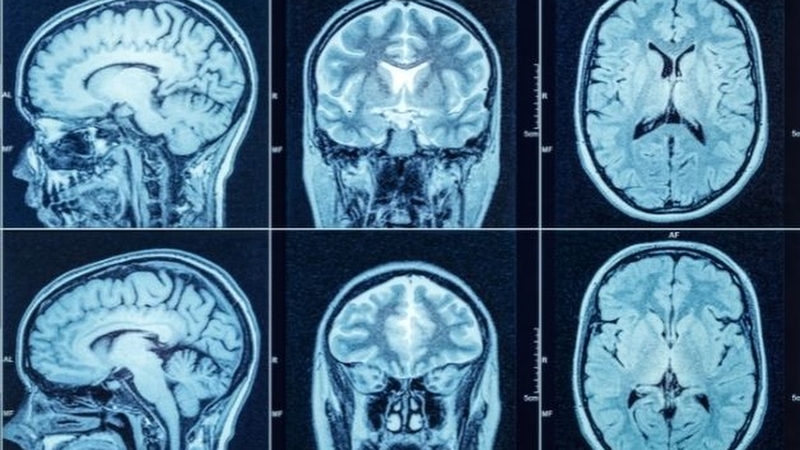

Bước 1: Chuẩn bị sẵn sàng trước khi phẫu thuật. Trước khi thực hiện ca phẫu thuật, bệnh nhân sẽ trải qua một cuộc kiểm tra sức khỏe tổng thể, bao gồm các xét nghiệm máu, chụp MRI hoặc CT để xác định chính xác vị trí và kích thước của tổn thương trong sọ não. Các bác sĩ cũng sẽ thảo luận về tiền sử y tế và các rủi ro có thể xảy ra để bệnh nhân hiểu rõ hơn về quá trình phẫu thuật.